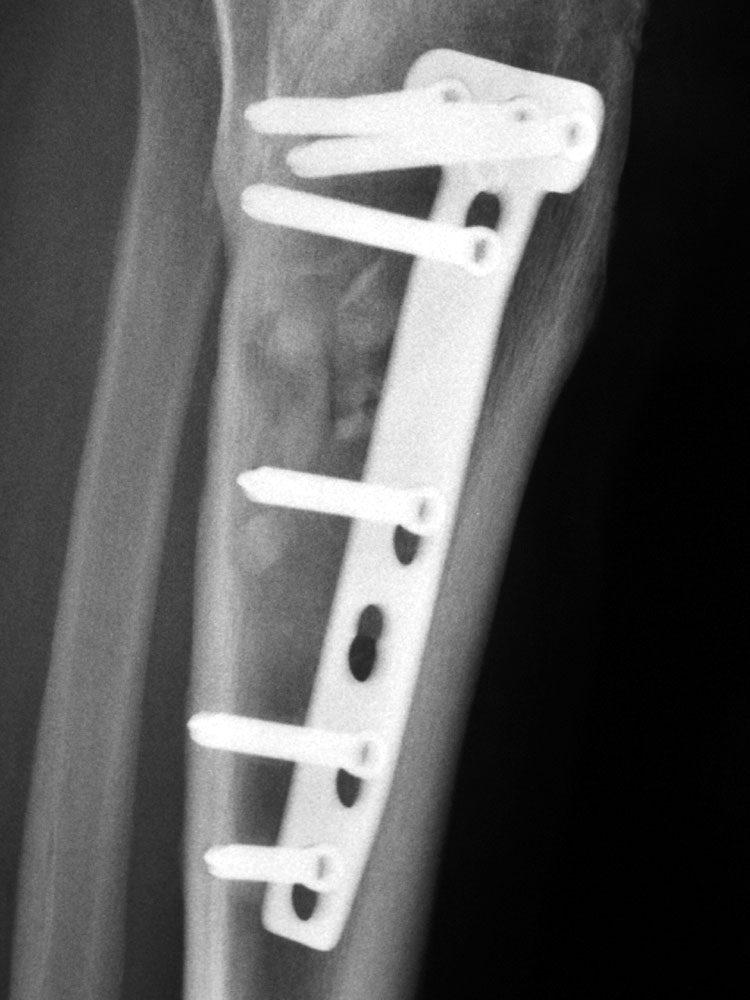

Röntgenbilder Salemspital Bern, 12. August 2005